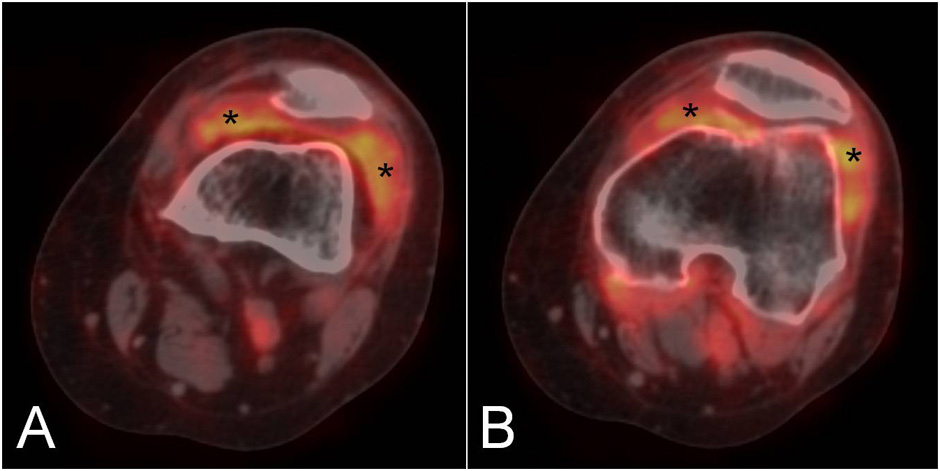

Figure 2

Two sequential PET/CT fused images of the knee in a patient with rheumatoid arthritis showing diffuse F18-FDG uptake in the medial and lateral paracondylar recesses (asterisks).

Figure 3

The coronal (A) and axial (B) PET/CT fused images of the wrist in a patient with rheumatoid arthritis demonstrate a focal area of F18-FDG uptake in the carpal tunnel, suggestive of flexor tendons tenosynovitis (asterisk). Tracer uptake is also observed in the metacarpophalangeal joints (C, arrows).

Although the main applications of PET and PET/CT are in the fields of oncology, neurology, psychiatry, and cardiology [47], novel data suggest a possible role of these techniques in rheumatology [4]. The main application is the diagnosis and follow-up of large vessel vasculitis [49, 50]. More recently RA patients have also been studied with this technique and their disease activity has been evaluated by calculating the standard uptake value (SUV) in the affected joints [51]. This method has allowed the measurement of a total score that includes all the joints involved by RA in a panoramic view of the patient. It has shown a good correlation with clinical evaluation and has also revealed involvement of the atlanto-axial joint in a few asymptomatic patients [52]. In another study, the results of PET imaging of the rheumatoid knee were in agreement with those obtained by more traditional imaging techniques, such as DCE-MRI and US [53]. In particular, PET uptake was significantly correlated with all MRI enhancement parameters as well as with synovial membrane thickness measured by US. PET uptake correlated with CRP and serum concentrations of metalloproteinase-3. After treatment with a single infusion of infliximab, an anti-TNFα biological agent, total SUV, MRI and laboratory findings significantly decreased [54]. Other anecdotal observations have confirmed the potential role of PET in the evaluation of treatment efficacy in RA patients by studying the wrist after etanercept administration [55]. One of the limitations of this method is that spatial resolution is low and imaging often suboptimal for small joints. Nevertheless, studies on hand and foot joints have been performed in RA with satisfying results [56]. Figures 2 and 3 show the results of PET/CT examination of the knee and hand, respectively, in patients with RA. In addition, PET/CT could be used for differential diagnosis between RA and seronegative spondyloarthritides (SpA) [57] especially by demonstrating a different anatomical pattern of uptake between these diseases. Evaluation of images of PET/CT scans of the shoulder, hip and knee joints have shown that FDG accumulated at the entheses in SpA and in the synovium in RA patients. In general, the main advantage of PET/CT examination in arthritis is the possibility of calculating a global score of the amount of inflammation present in the joints. A clear drawback is that, due to the high amount of ionising radiation, it cannot be used in repeated follow-up examinations. To reduce radiation exposuree, PET/CT could be used to obtain functional and morphological information at baseline, and PET alone could be repeated over time.